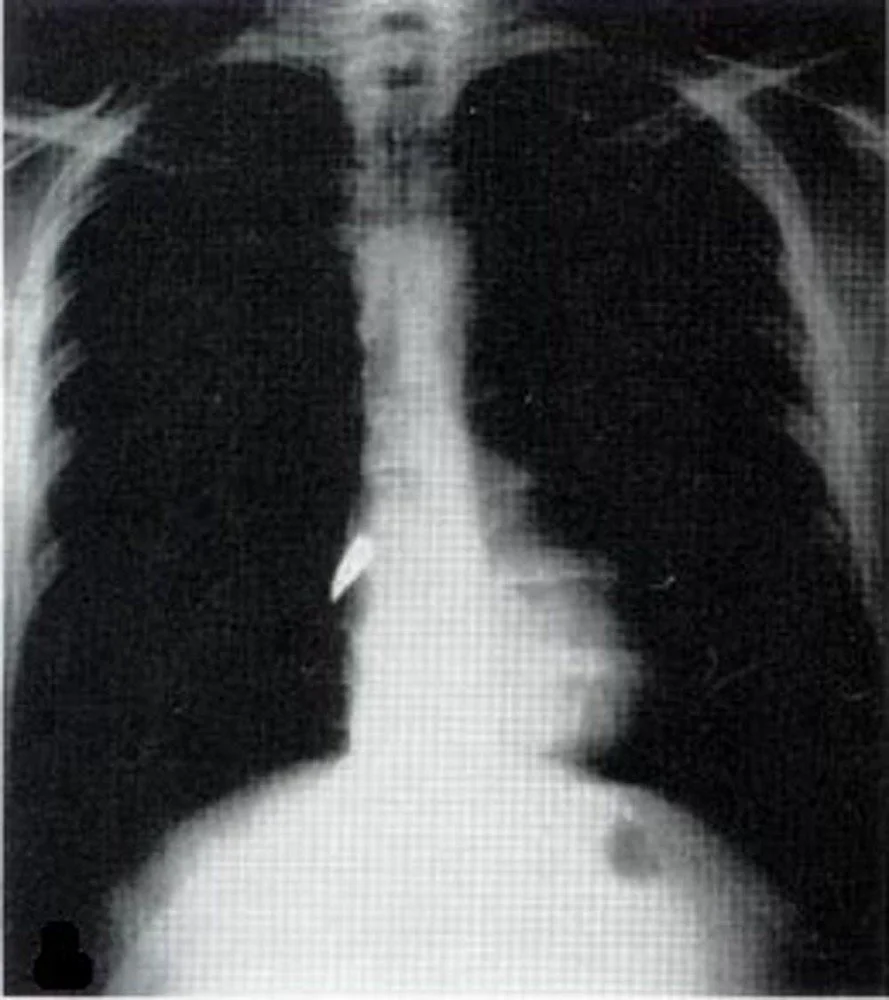

Chest radiograph reveals a bullet lodged closely to the right heart border.